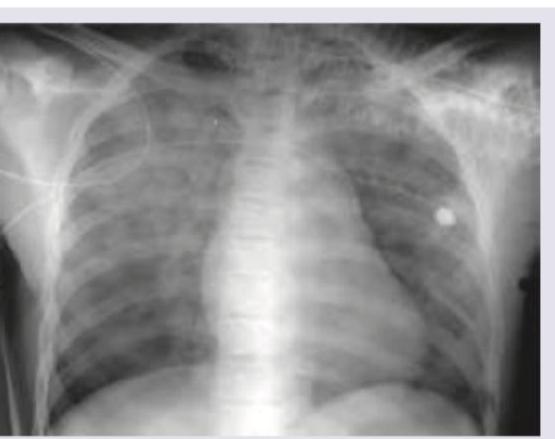

A patient in ICU was given blood transfusion. 3 hours later SpO2 is reduced to 75% with respiratory difficulty. CVP is 15 cm water and PCWP is 25 mm Hg . CXR is shown below. What is the diagnosis?

Explanation: ***Transfusion associated circulatory overload*** - The combination of **respiratory difficulty**, **reduced SpO2**, **elevated CVP (15 cm water)**, and **markedly elevated PCWP (25 mm Hg)** after a blood transfusion strongly indicates hydrostatic pulmonary edema due to fluid overload. - The CXR image showing **diffuse bilateral infiltrates** (pulmonary edema) further supports this diagnosis, especially with the elevated cardiac filling pressures. *Tension pneumothorax* - A tension pneumothorax would present with **unilateral lung collapse**, **tracheal deviation**, and potentially **hypotension**, none of which are explicitly described or suggested by the CXR. - While it causes respiratory distress, the hemodynamic parameters (CVP and PCWP) and bilateral CXR findings are inconsistent with a pneumothorax. *Transfusion related acute lung injury* - TRALI also causes acute respiratory distress and hypoxemia after transfusion, but it is characterized by **non-cardiogenic pulmonary edema** with a **normal or low CVP** and **normal or mildly elevated PCWP** (<18 mm Hg), differentiating it from TACO. - The elevated CVP and PCWP strongly point away from TRALI, which is immune-mediated and involves capillary leakage. *Mismatched blood transfusion* - An acute hemolytic transfusion reaction (mismatched blood transfusion) typically presents with symptoms such as **fever, chills, flank pain, hemoglobinuria**, and potentially **DIC** or **renal failure**. - While it's a serious transfusion reaction, the primary clinical presentation and elevated cardiac filling pressures are not characteristic of an acute hemolytic reaction.